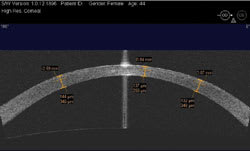

Postoperatively, high-resolution corneal scans detail the actual thickness of the flap and the residual stroma. This is useful in ensuring that enough residual stroma will remain after an enhancement. For instance, the patient in Figure 5 had LASIK 6 years prior to presenting to us with -2 D. Her medical file was unattainable so there was no preoperative or intraoperative information available to us.

We could perform the ultrasound pachymetry, but there would be no differentiating between the flap and the stromal bed thickness. Alternatively, we could take this patient into the operating room, lift the flap and perform the ultrasound pachymetry on the stromal bed, and if there was enough stromal bed, we could then perform the excimer enhancement.

The patient in Figure 6 had LASIK performed 4 years ago and presented to us for a possible enhancement of -5 D. In her case, there was too little stroma left (255 μm) and she could have been put at risk for ectasia if we performed an enhancement. Another option would be to perform PRK. By measuring the thickness of the epithelium and the thickness of the flap, we could see if there was enough stroma within the flap to treat the residual refractive error without creating a buttonhole.

Figure 5. High-resolution corneal OCT scan in a patient 6 years after LASIK who presented for possible enhancement of -2 D. Flap thickness is 148 μm and the stromal bed is 351 μm enough for the enhancement. | Figure 6. High-resolution corneal OCT scan in a patient 4 years after LASIK. The patient presented for possible enhancement of -5 D residual myopia. The residual stroma is too thin (255 μm) for further LASIK enhancements. |